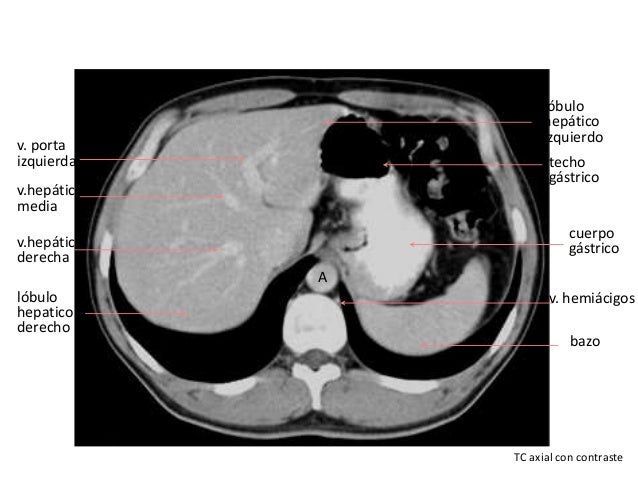

Tac abdominal con contraste. Abdomen Por lo general, este examen se realiza con el fin de diagnosticar la causa de dolor abdominal y enfermedades intestinales de colon La exploración por TAC del abdomen / pelvis también se realiza para Visualizar el hígado, el bazo, el páncreas, la próstata y los riñones, entre otros. Tomografia Tomografia Axial Tomografia Torax en Caracas Tomografía, Tomografía de Abdomen y Pelvis, Tomografía con Doble Contraste, TAC de Cráneo, Angiotac, Urotac, TAC de Senos Paranasales Axiales y Coronales, Angiotac Coronario, Tomografía con Reconstrucción Volumétrica, Broncoscopia Virtual, Mamografía, Mamografía con Implantes, Tomo Mamografía 3D, Co. Muchos pacientes también reciben un agente de contraste con yodo en forma intravenosa (inyectado en vena), para ayudar a evaluar los vasos sanguíneos y los órganos tales como el hígado, los riñones y el páncreas Cuando ingrese en el dispositivo de exploración por TAC, podría ver haces de luces especiales proyectados sobre su cuerpo.

TC do abdómen com contraste Na tomografia computorizada (TC) abdominal com contraste pretendese avaliar o comportamento vascular das estruturas em estudo Os produtos de contraste iodados (à base de iodo) são aplicados por via endovenosa e permitem ampliar o contraste entre as estruturas com distintos fluxos sanguíneos, sendo particularmente útil na avaliação das estruturas hipervascularizadas, como por exemplo tumores ou inflamações. Tac de abdomen o de abdomen y pelvis Con contraste endovenoso y, en algunos casos, contraste oral y endovenoso El tac de abdomen permite ver lesiones en cualquiera de los órganos abdominopelvianos, léase hígado, páncreas estómago, riñones, intestinos, vejiga, próstata, útero, ovarios, lesiones como tumores, quistes o seguimiento post quirúrgico de alguno de ellos. En muchas ocasiones, una tomografía computarizada del abdomen se realiza con una de la pelvis El examen debe tardar menos de 30 minutos Preparación para el examen Usted necesitará tener un colorante especial, llamado medio de contraste, en el cuerpo antes de algunos exámenes El medio de contraste ayuda a que ciertas áreas se vean mejor.

Servicios incluidos AngioTAC de la zona abdominal;. TC abdominal con contraste se lleva a cabo en función del tipo específico al que pertenece el escáner porque la investigación estándar en cualquier caso es menos precisa en comparación con un resfriado. El TAC Abdominal es la prueba idónea para una vista general del abdomen porque gracias a la administración de contraste se pueden valorar todas las estructuras abdominales El contraste es una sustancia líquida que puede ser administrada bebida o inyectada y ayuda a la visualización de estas partes del cuerpo proporcionando mayor información diagnóstica.